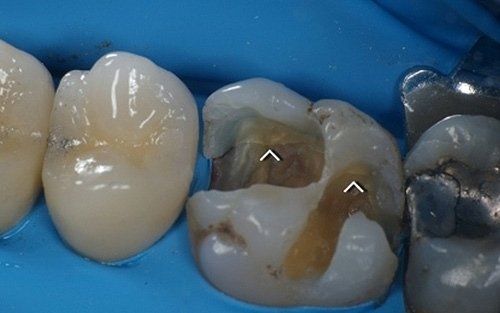

Upon removal of the old restoration, the diagnosis will be confirmed by visualising fracture lines that may involve various areas of the tooth (usually the base of one or more cusps, extending to the entire roof of the pulp chamber and root extension). Not all cracks are equally severe: we believe that preserving the vitality of the pulp, where possible, along with protecting the affected cusps from cracking, is the most conservative and long-term effective therapy for tooth health. In the "Direct restorative dentistry" section and especially in the "Indirect restorative dentistry" section, you will find a series of restorative solutions for the cracked tooth.